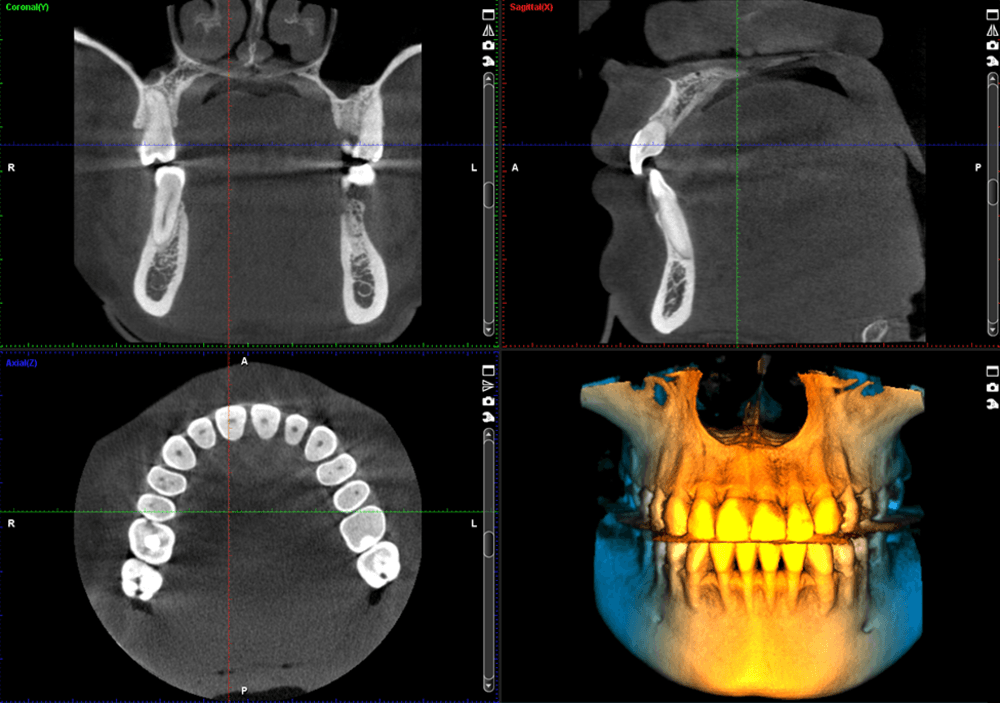

Planmeca ProMax® 3D

Meet the Planmeca ProMax® 3D imaging family, a comprehensive suite of solutions tailored to meet the unique demands of dental practices. With unparalleled image quality and cutting-edge technology, these systems provide practitioners with the versatility and precision needed for accurate diagnostics and treatment planning.

Discover the Planmeca ProMax® 3D family, meticulously designed to meet the needs of every dental practice. Known for its unparalleled image quality, each system reflects Planmeca's commitment to excellence. Equipped with noise reduction technology, these units deliver unmatched image clarity. Enjoy True Extraoral bitewings, segmented pans, and AutoFocus for crystal clear pan images every time. Available features like Planmeca Ultra Low Dose™ and Planmeca CALM® for patient safety